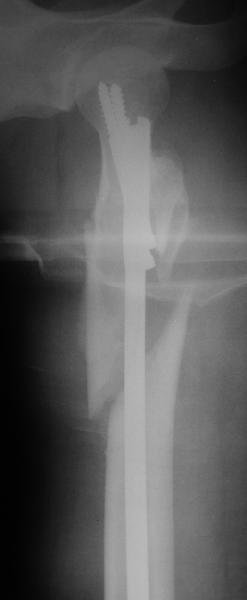

Спасибо, все практически так и получилось - на счастье в наших краях на днях была конференция по ожогам, на которую представители "Деоста" ехали на выставку. Попутно захватили нам реконструкционный гвоздик ChM с набором инструментов.

Оперировали вчера. Не сказать, что все прошло гладко - вертельная область была расколота и в сагиттальной, и во фронтальной плоскости, гвоздь попал в перелом и сместился кзади, что заметили уже после введения винтов, пришлось все извлечь и переставить. Снимки в приложении. Буду признателен за комментарии.

Если честно, мне не нравится стояние отломков

проксимального отдела. На мой взгляд причина в недостаточной осевой тракции сегмента перед этапом дистального блокирования. Если это действительно так, я бы попробовалудалить дистальные блокирующие винты, дать осевую тракцию(дистрактор, ортопедический стол, др.) и повторное дистальное

блокирование.

уважаемый А.Ч.! Не уверен, что отломки сопоставлены хорошо. Особенно плохо лбстоят дела с малым вертелом. Клинический исход по-видимому будет неудовлетворительным.